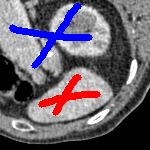

7.4 Alternative Selective Methods

In order to further establish the robustness of our method, we now introduce the results of testing our approach against competing interactive segmentation methods on a larger data set. The results are presented in Fig. 17, showing a boxplot of accuracy in terms of TC on a set of 30 CT images (excluding outliers). The target structure we consider is the spleen, as this consists of a relatively homogeneous foreground, appropriate for the approach considered. The data has been manually contoured providing ground truth data for the image set. We compare CAC Nguyen:12 and SRW SRW against our method with five variations of user input for each image. It is worth emphasising here that the input used in the tests is identical for each approach and was not refined in any way. It was designed to mimic what a user, unfamiliar with each approach, might select intuitively. A representative example for three images is shown in Fig. 18. This shows foreground (red) and background (blue) user input regions. For our method, we define the red region as as discussed in §1 and enforce hard constraints on the blue region. We refer to the results of the proposed approach using this input as Ours (i). We also include results of randomising the user input in an identical way to §7.3. For each image we generate 1000 simulated user input choices, which we present as Ours (ii). It is important to note that the difference between Ours (i) and (ii) is only the definition of . The method and parameters are fixed between each.

The performance of CAC Nguyen:12 is very good, as shown in Fig. 17. We have included an additional figure to highlight the difference between CAC and Ours (i) and (ii) more precisely. This is shown in Fig. 19 (this is the same as Fig. 17 with TC restricted to [0.8,1]). Here we can see that the proposed approach has a slightly better median (0.96 compared to 0.94) and is generally more consistent than CAC. This is particularly evident when considering the worst TC results of CAC () against ours ().

In Fig. 17 it can be seen that our method exceeds the performance of SRW by a large margin (0.66 compared to 0.95). One possible reason for this is that the input used, as displayed in Fig. 18, is restricted to be as intuitive as possible. SRW is capable of achieving improved results with more elaborate foreground/background input. However, it is generally reliant on a trial and error approach which is not ideal in practice. This highlights an important advantage of our method. It is able to achieve a high standard of results with simple user input. This is reinforced by considering Ours (ii), where the results of 30000 random variations of the user input does not cause a drop off in accuracy compared to the 150 manual user input selections. Again, this can be seen more clearly in Fig. 19. In fact, the results for the proposed approach with the random input are slightly better than with the manual input. This underlines the robustness to user input in the model, which is a vital aspect of selective segmentation.